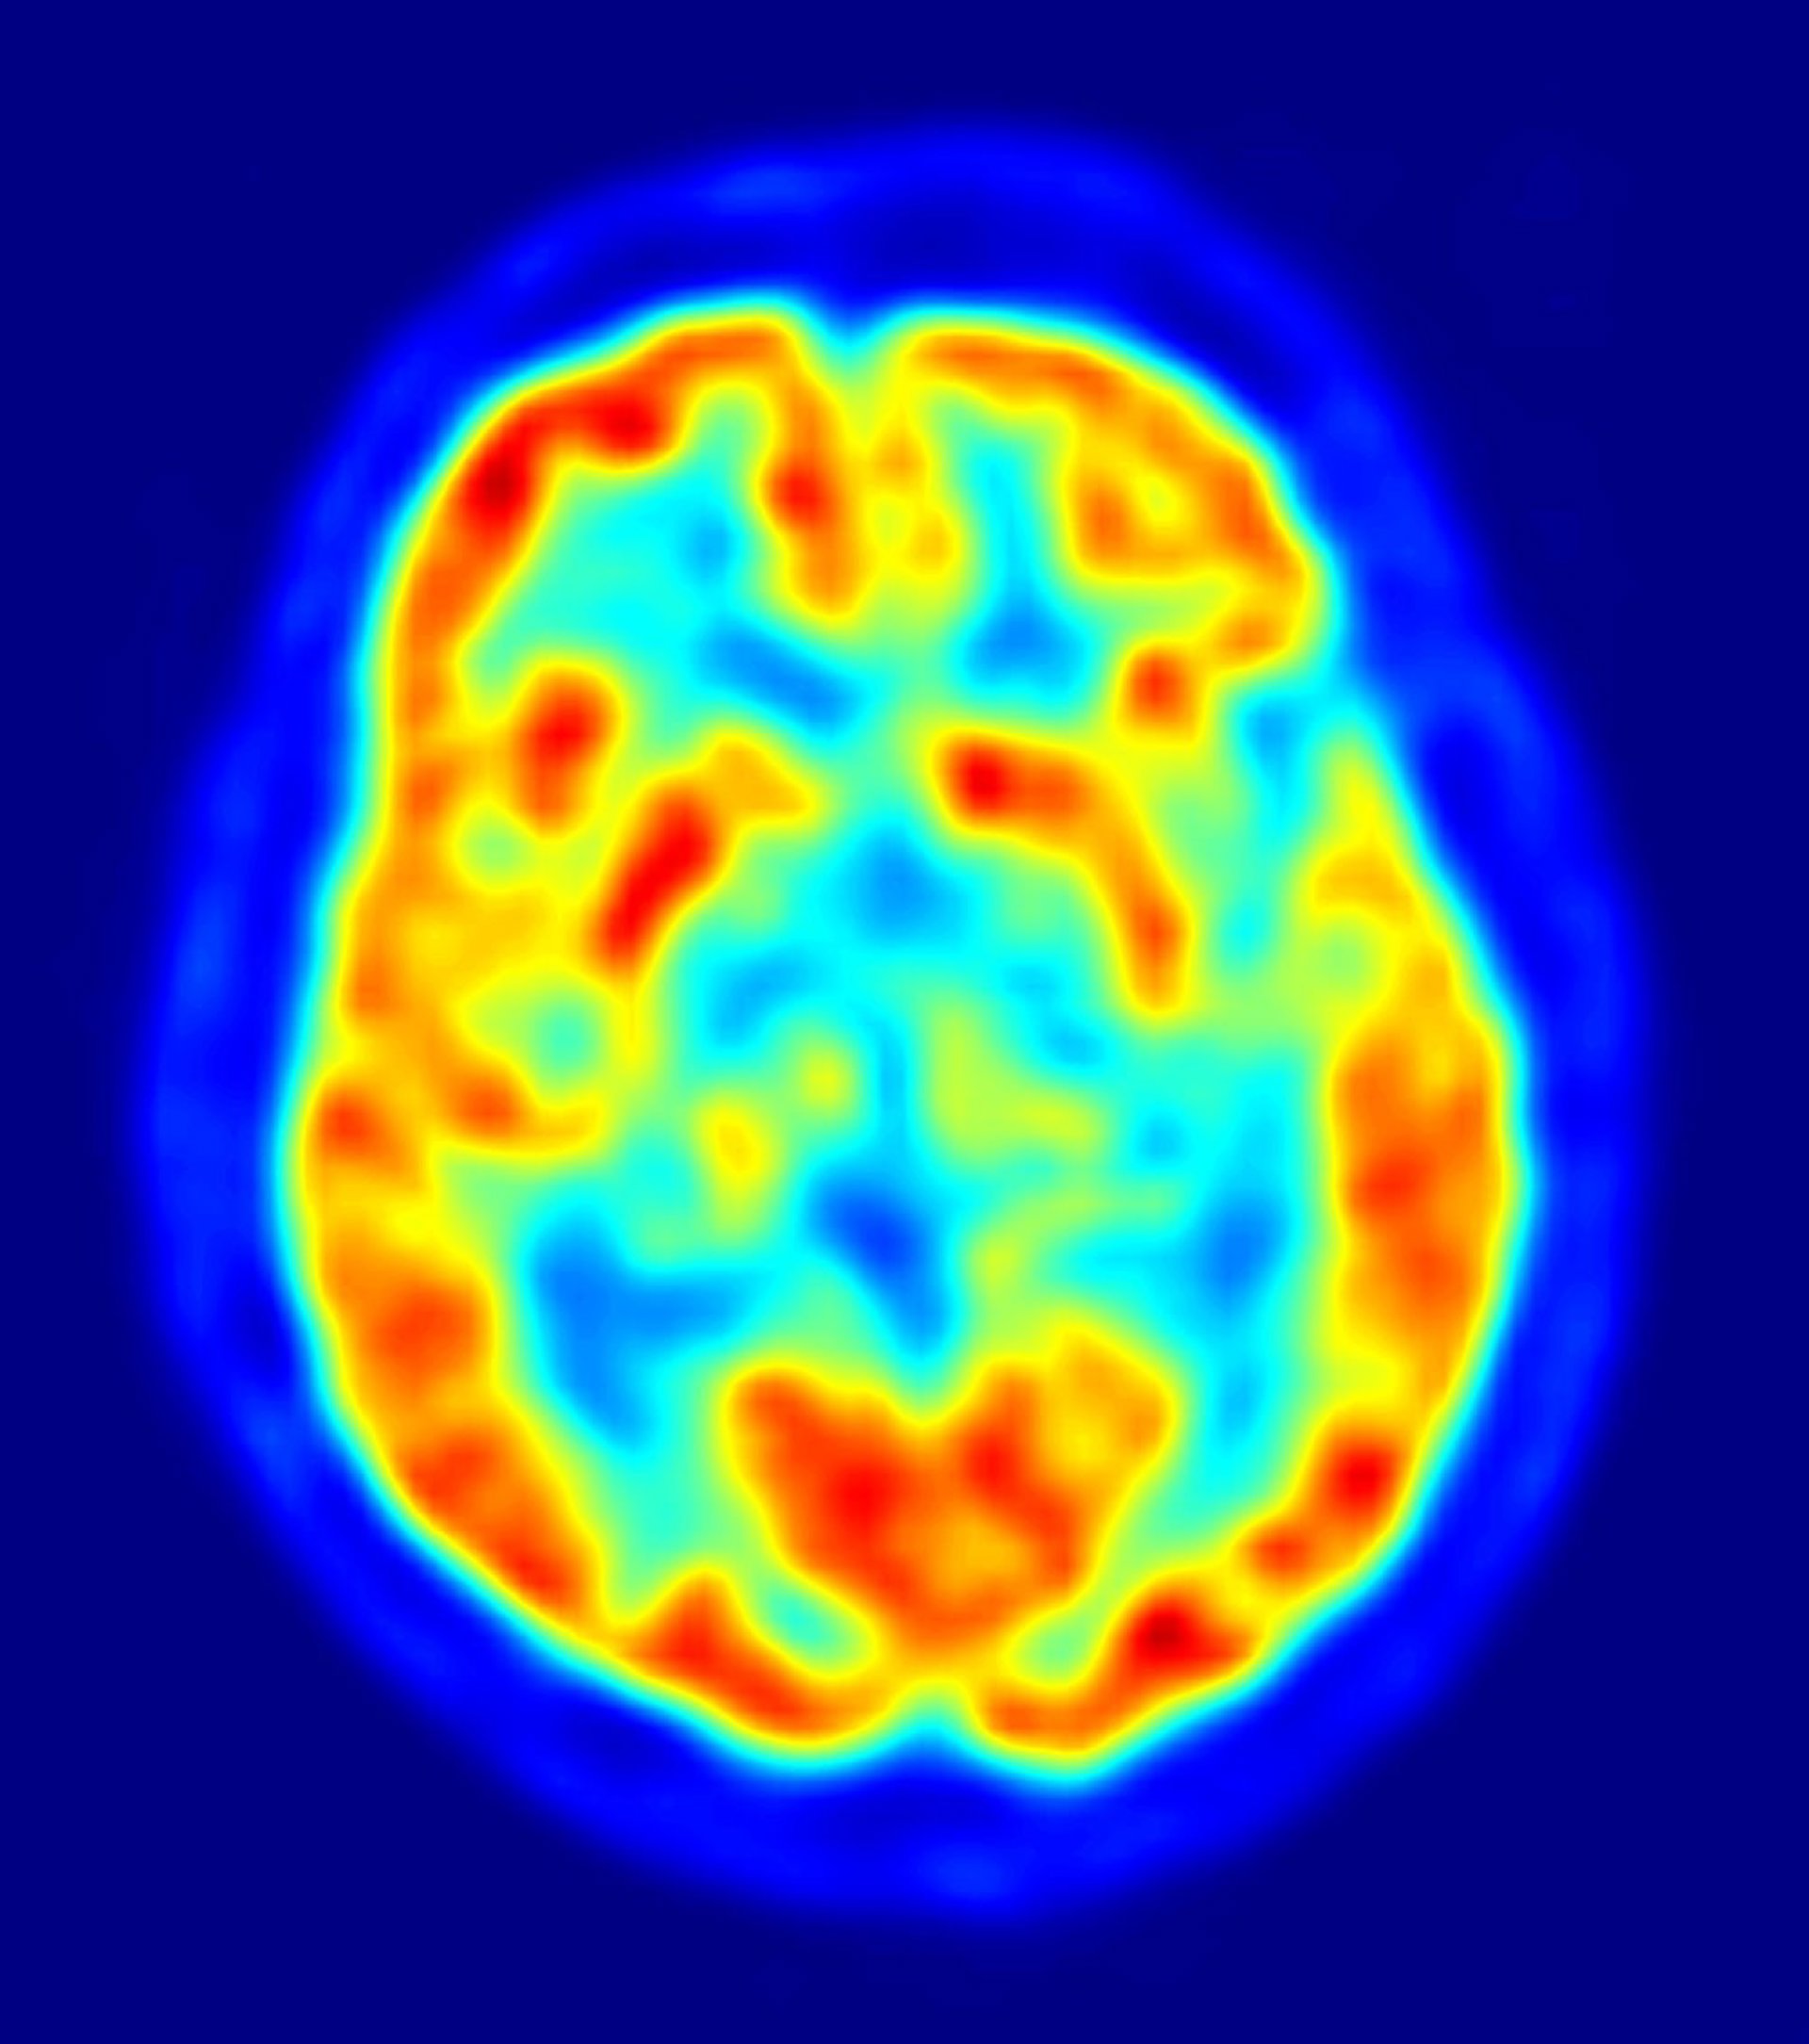

En Canarias, las enfermedades neurológicas afectan a unas 300.000 personas, lo que equivale al 16 por ciento de la población total del archipiélago; además, se estima que el aumento de la esperanza de vida en España producirá un incremento de la frecuencia de estas enfermedades en las próximas décadas.

Aunque las enfermedades neurológicas más frecuentes y conocidas por la sociedad son las demencias (entre las que se incluye la enfermedad de Alzheimer), el ictus, la epilepsia, la enfermedad de Parkinson, la esclerosis múltiple o la migraña, también hay otras enfermedades neurodegenerativas y neuromusculares como la esclerosis lateral amiotrófica, las distrofias musculares o las distonias.